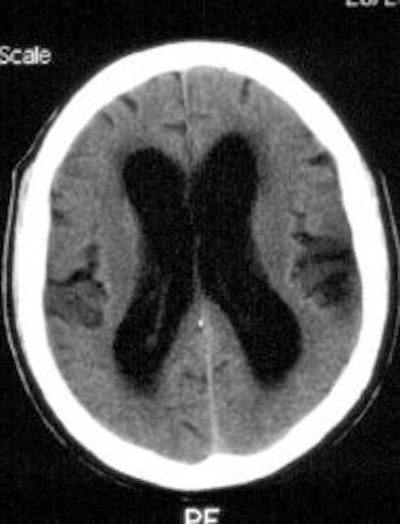

Normal Pressure Hydrocephalus: A CSF examination using In-111 DPTA is shown below. The 24 hour image demonstrates ventricular acitivity and persistent activity in the basal cisterns without evidence of activity over the convexities. Ventricular activity persists on the 48 hour exam. Some transependymal intracerebral activity is also suggested on the later images. The CT scan demonstrates the characteristic findings in NPH with ventriculomegaly out of proportion to sulcal atrophy (Click CT for additional images). |

Ventriculomegaly secondary to atrophy (Hydrocephalus ex-vacuo):

NPH is characterized by the clinical triad of mental status changes, incontinence, and ataxia, with hydrocephalus and normal CSF pressures. The scintigraphic examination demonstrates a slow ascent over the convexities with little activity seen over the vertex. Ventricular reflux with delayed clearance of ventricular activity is also seen. Late intracerebral activity can be seen and is secondary to transependymal uptake of the tracer. Surgical shunting of CSF can potentially reverse this progressive disorder. Correlation with a positive examination and benefit from shunting is poor.